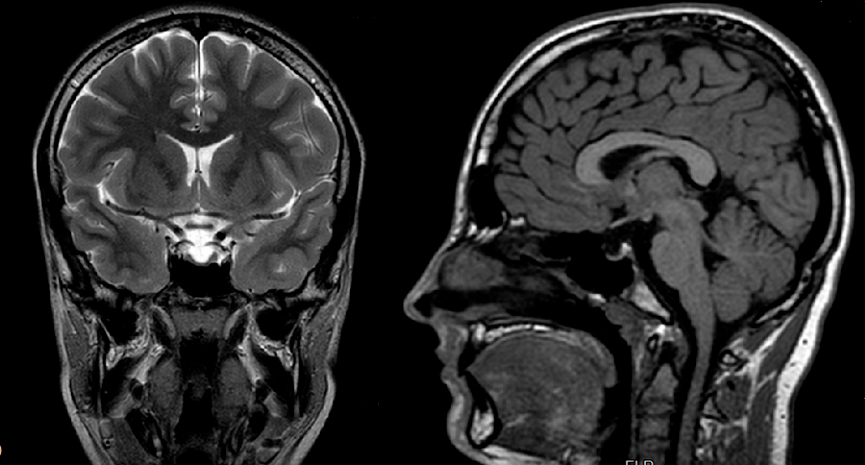

Es valorado por Oftalmología, descartando edema de papila. Se solicita estudio hormonal hipofisario, normal y resonancia magnética cerebral que informa de hipófisis aplanada (Fig. 1). Se realiza punción lumbar, con presión de apertura de 14 cmH2O y salida de líquido cefalorraquídeo lenta. Análisis y cultivo del líquido normal.

Figura 1. RM cerebral. Corte coronal y sagital.